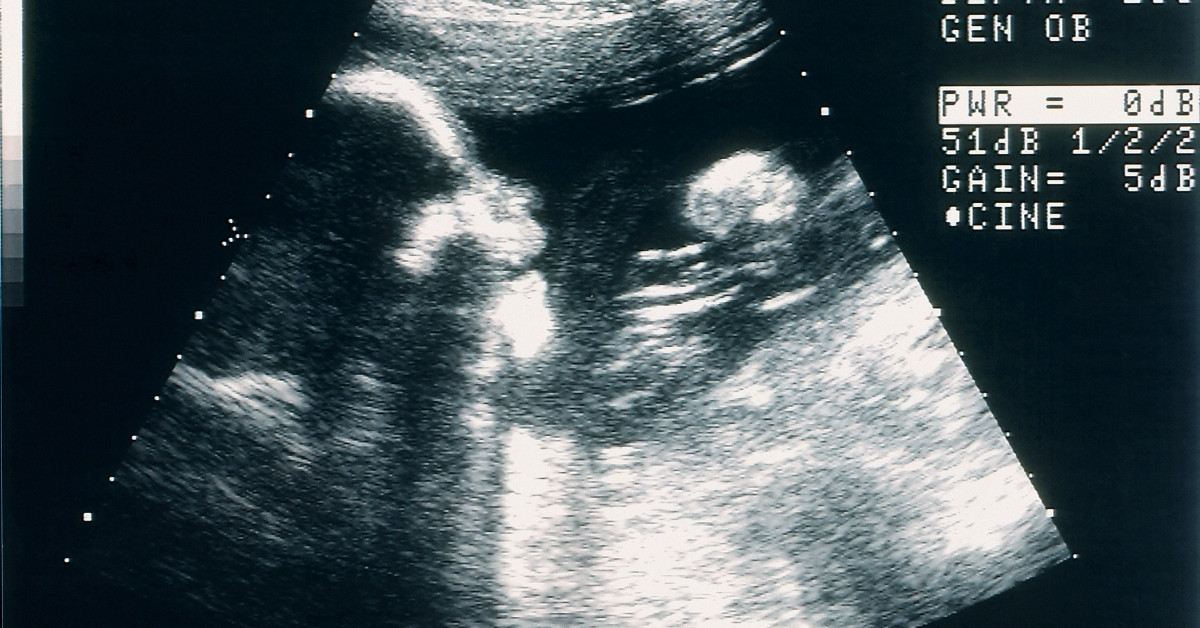

TIL the Japanese online flea market, Mercari, had to ban ultrasound photos and positive pregnancy tests from its marketplace app because people were allegedly using them to fake pregnancies in order to extort money or blackmail their partners.